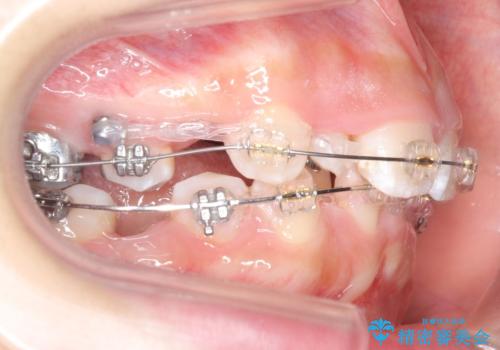

- 矯正装置

- プラスチックブラケット

奥歯のかみ合わせもずれていたため、上の奥歯を後ろに下げる処置をミニスクリューを用いて行いました。